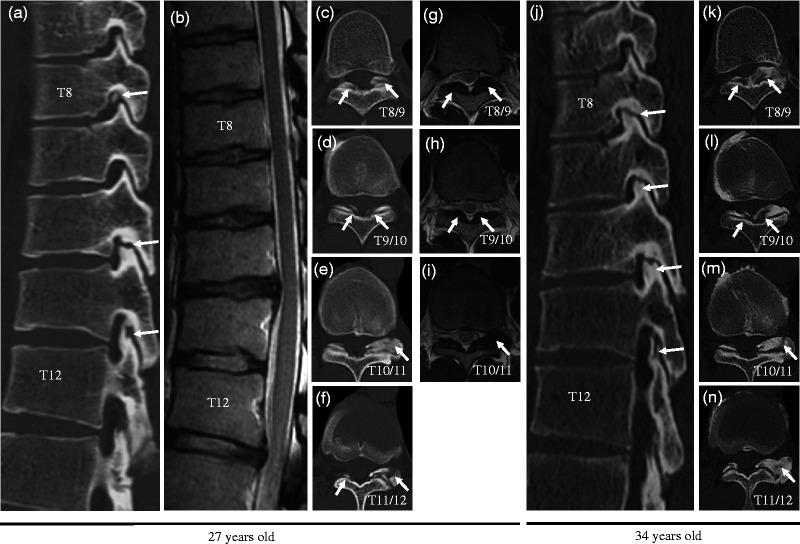

Both systemic and local factors might influence the development of ossification of the ligamentum flavum (OLF); however, whether specific physical activities play a role in the development of OLF remains unclear. This report presents two cases of thoracic radiculopathy owing to progressive enlargement of thoracic OLF within a few years in Japanese professional baseball pitchers. Two left-handed, Japanese, professional baseball pitchers in their 20s experienced thoracic radiating pain. Mild hypesthesia of the lower thoracic vertebral levels was observed, and an increase in the size of the OLF within a few years was identified in the lower thoracic spine using computed tomography and magnetic resonance imaging. Neither patient exhibited myelopathy and were, therefore, treated conservatively. Both patients were able to return to playing in top condition within 4 months after onset. The findings in these cases suggest that thoracic OLF might increase in size and become exacerbated in certain individuals, such as professional pitchers, who experience repeated, localized, mechanical stress on the thoracic spine, irrespective of age.